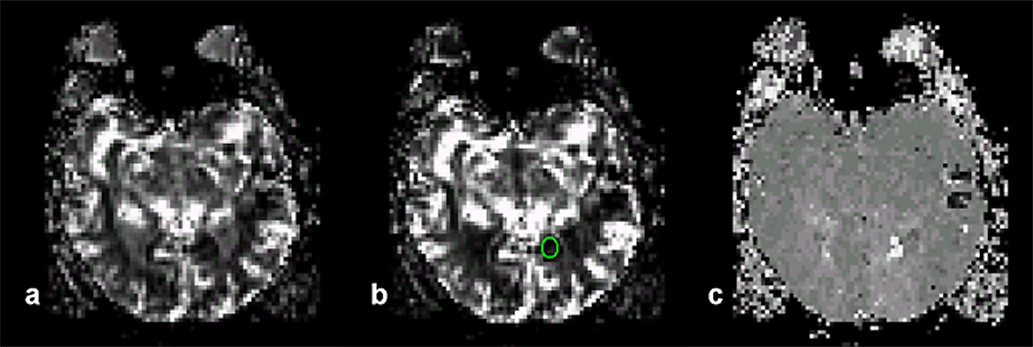

Figura 16-08:

Magnetic resonance mammography (MRM). (a) Image from a data set of 44 dynamic slices. T1-weighted RF-spoiled gradient-echo sequence. The ROI is positioned in the tumor.

(b) Same patient: Parametric map based on the T1-weighted image time series: ma­xi­mum en­­han­­ce­­ment image.

(c) Dynamic uptake curve of an ECF con­trast agent in the breast lesion depicted in (a) and (b).